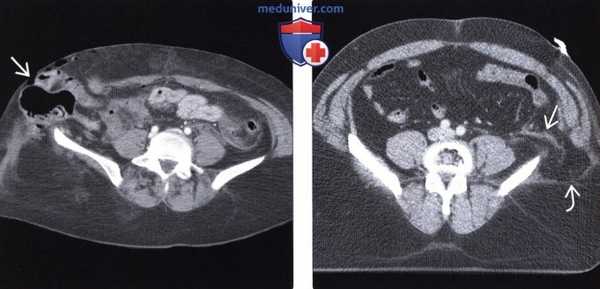

(Слева) На аксиальной КТ с контрастом визуализируются тонкая и ободочная кишка, выбухающие наружу сквозь травматический дефект в брюшной стенке. При операции в некоторых сегментах тонкой кишки были обнаружены разрывы серозной оболочки и ее повреждения отрывного характера, из-за чего потребовалось выполнение резекции.

(Справа) На аксиальной КТ с контрастным усилением определяется травматическая поясничная грыжа с выпадением внутрибрюшной жировой клетчатки, прикрытой только широчайшей мышцей спины. Также обратите внимание на инфильтрацию внутрибрюшной клетчатки возле грыжи. На операции был выявлен разрыв серозной оболочки нисходящей ободочной кишки. (Слева) На аксиальной КТ с контрастным усилением определяются петли тонкой кишки, не усиливающиеся при контрастировании, в большом количестве выбухающие сквозь травматический дефект в брюшной стенке с правой стороны. Определяются также признаки активного артериального кровотечения. Большая часть кишки была обнаружена нежизнеспособной при операции.

(Справа) На аксиальной КТ с контрастным усилением определяется разрыв мышц брюшной стенки в нижних отделах слева, кроме того, мышцы оторваны от места своего прикрепления к гребню подвздошной кости. Обратите внимание на наличие подкожной гематомы в прилежащих отделах. Это - типичный пример повреждений, возникающих при неправильно зафиксированном ремне безопасности.

(Справа) На аксиальной КТ с контрастным усилением определяется травматическая поясничная грыжа с выпадением внутрибрюшной жировой клетчатки, прикрытой только широчайшей мышцей спины. Также обратите внимание на инфильтрацию внутрибрюшной клетчатки возле грыжи. На операции был выявлен разрыв серозной оболочки нисходящей ободочной кишки.

(Слева) На аксиальной КТ с контрастным усилением определяются петли тонкой кишки, не усиливающиеся при контрастировании, в большом количестве выбухающие сквозь травматический дефект в брюшной стенке с правой стороны. Определяются также признаки активного артериального кровотечения. Большая часть кишки была обнаружена нежизнеспособной при операции.